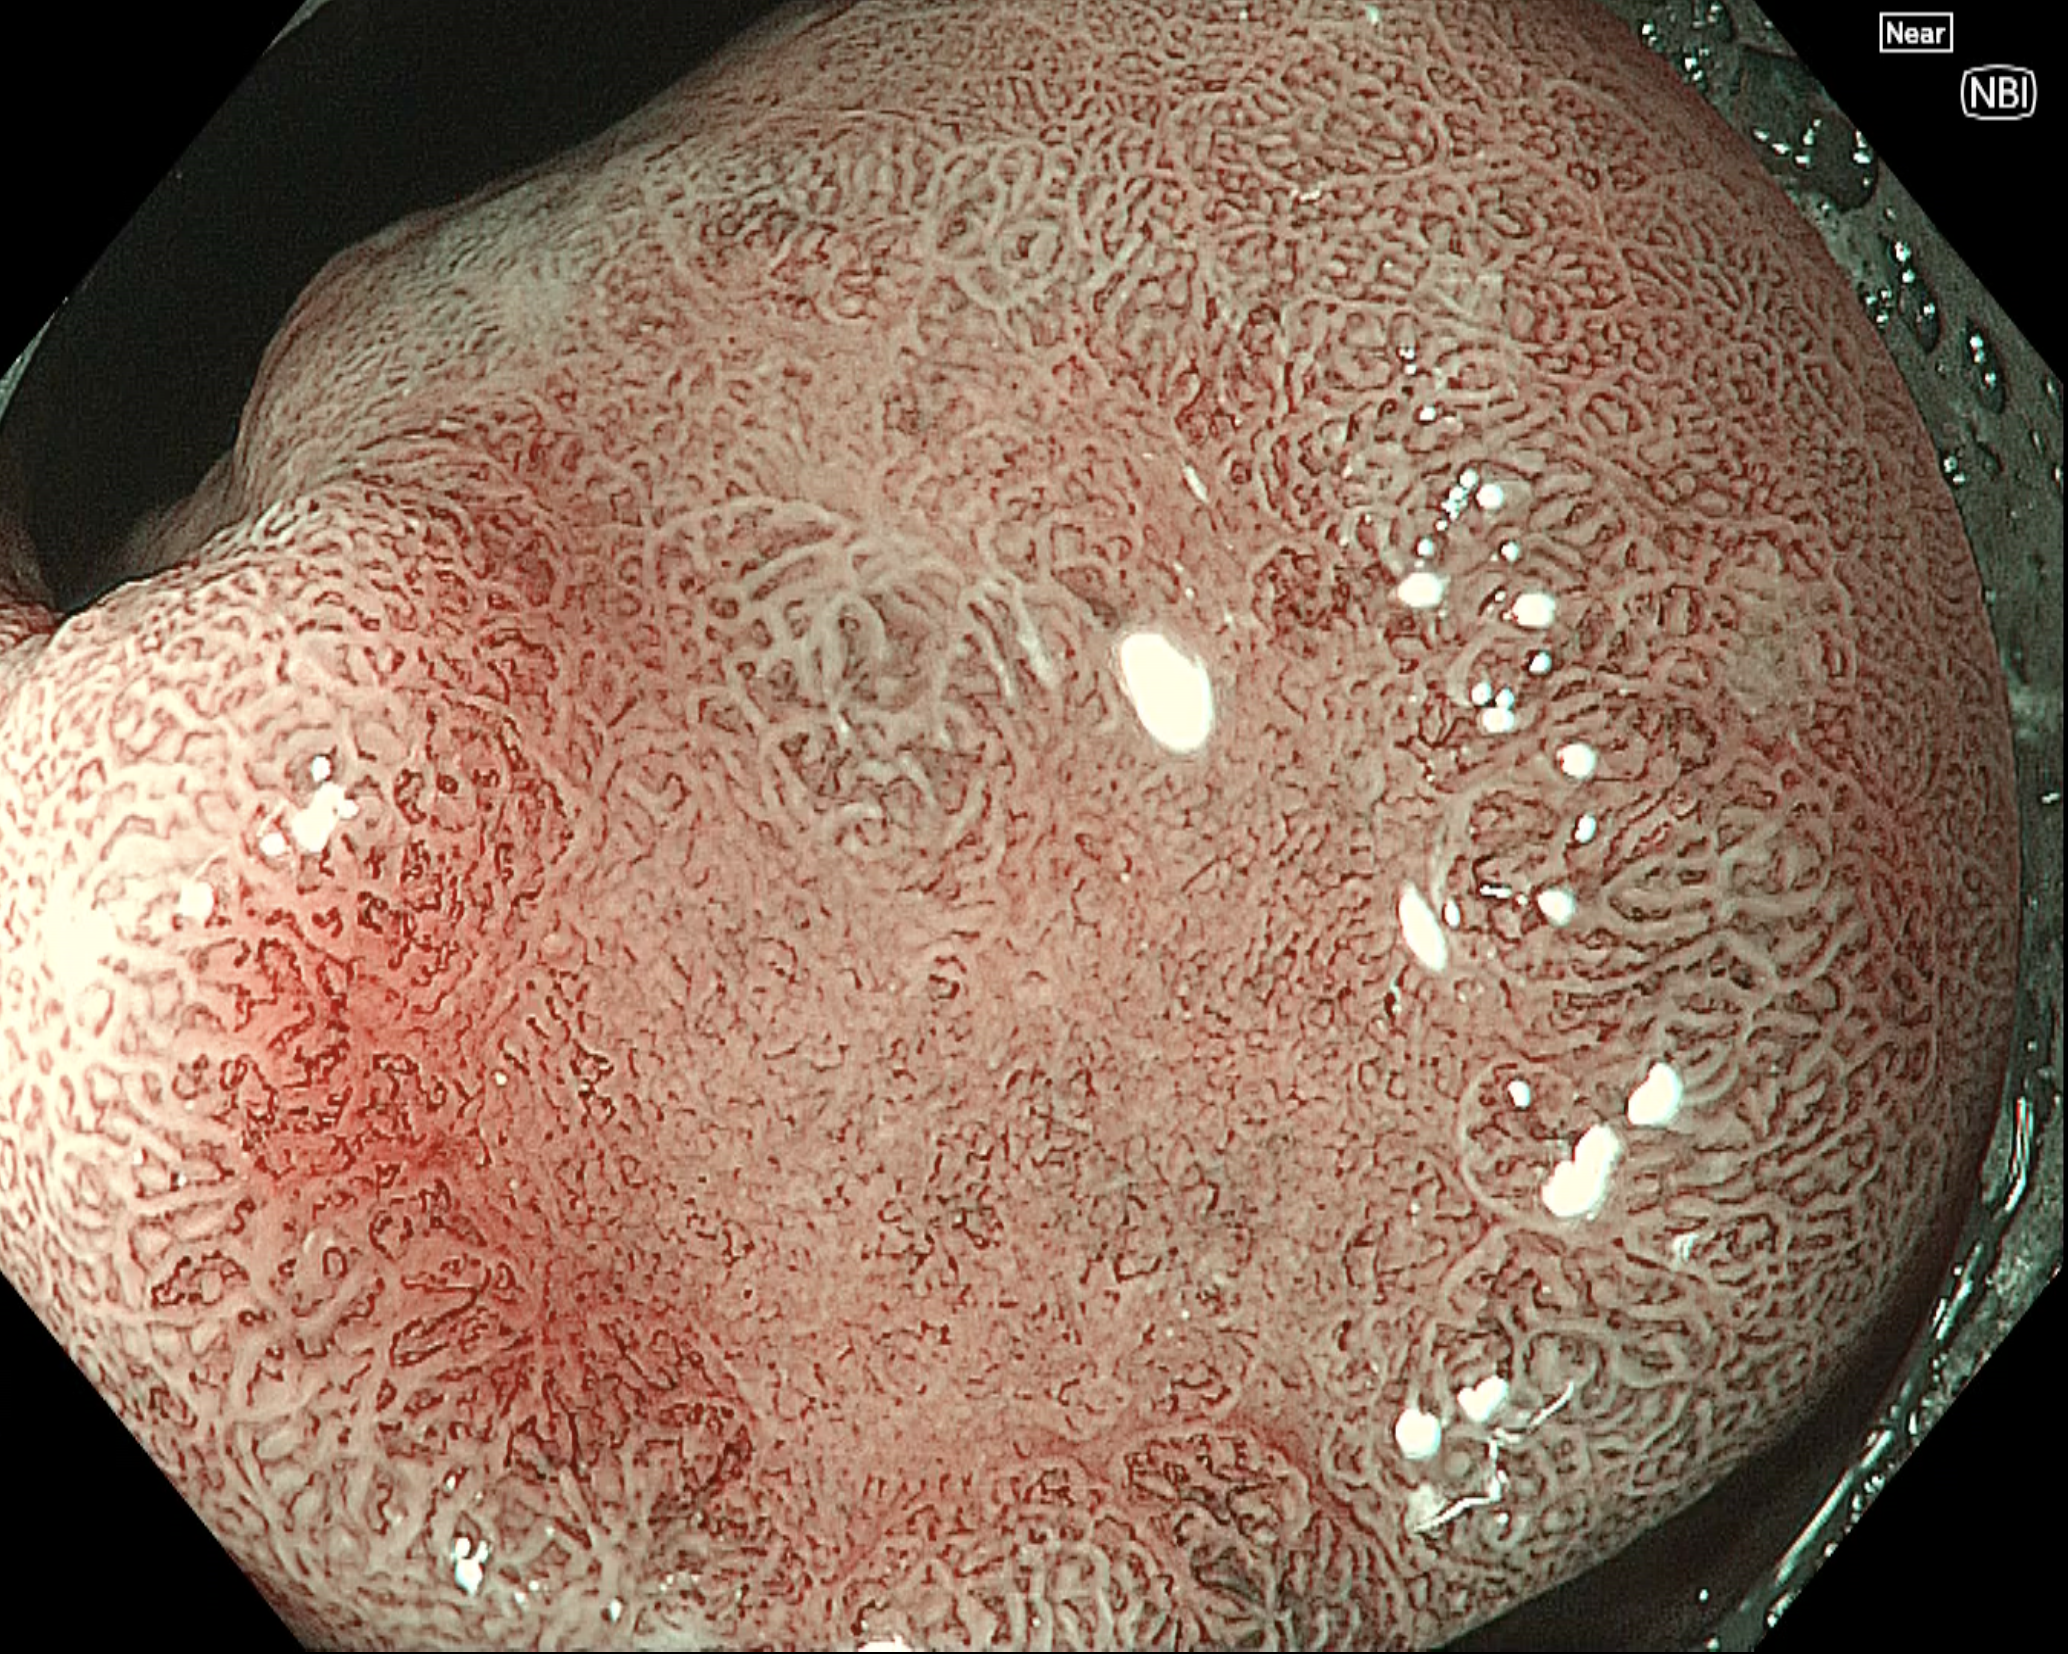

• NBI観察(近接拡大)

強調設定:B8

図4

NBIを併用した近接拡大(near focus)観察では病変部と非病変部の境界(Demarcation line;DL)を全周で確認できる。腫瘍肛門側の表面微細構造は不鮮明化、口側には不整な管状構造、その境界部には生検による再生粘膜を認める。